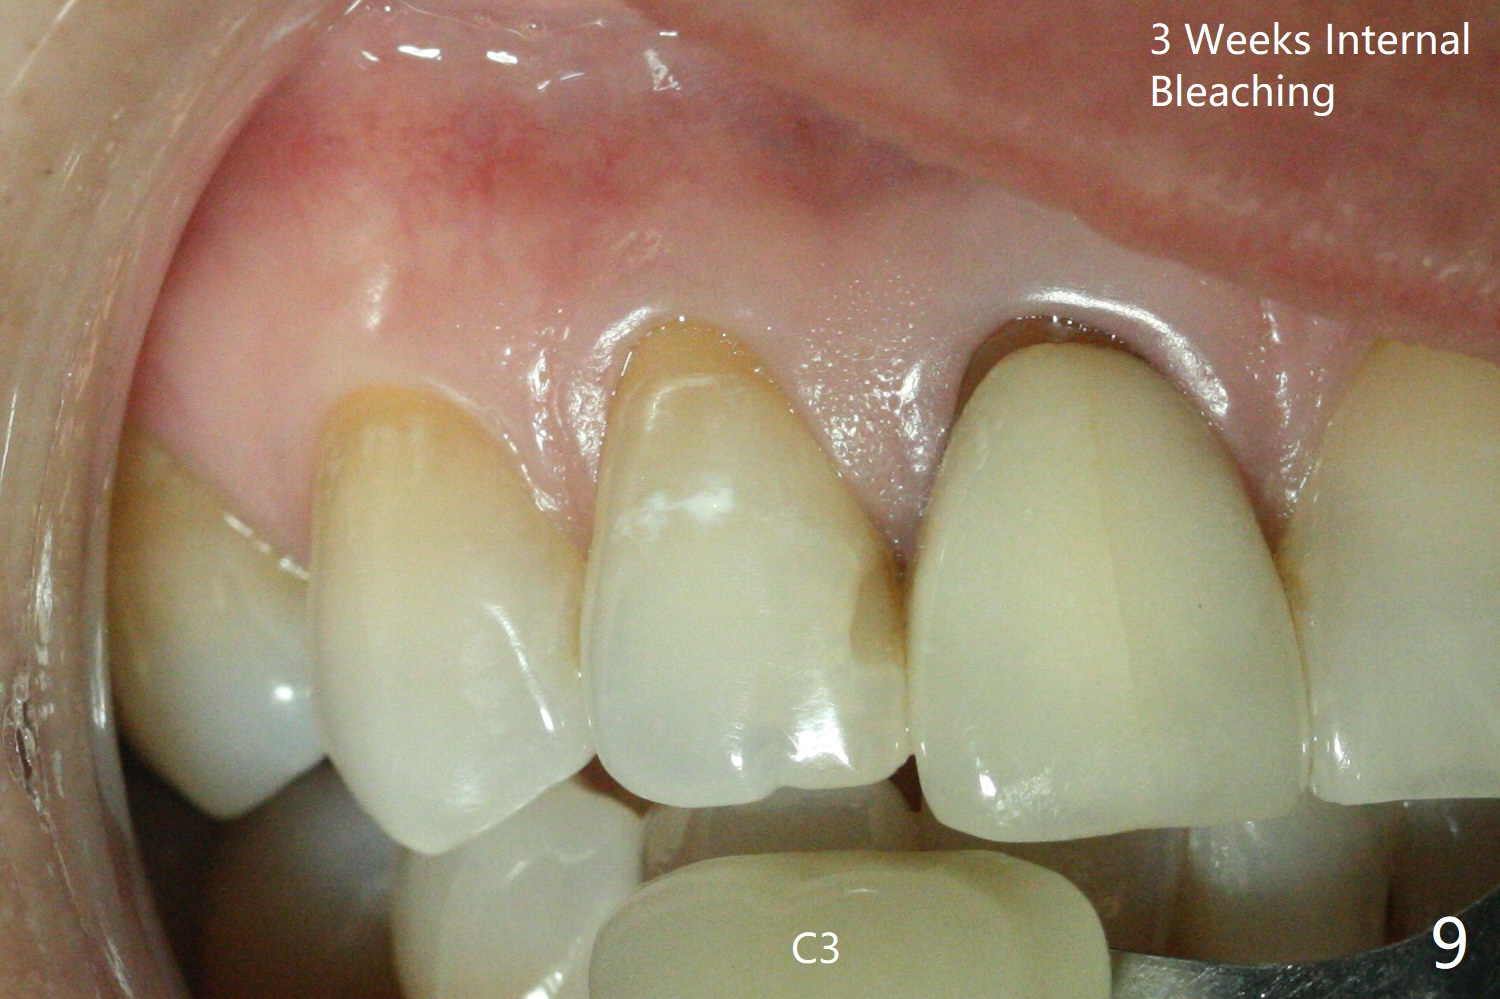

A 46-year-old woman requests a crown for the discolored tooth #7 (Fig.1,2) with mesiolingual composite (Fig.3 C) and periapical radiolucency (*). After RCT (Fig.4,5) with sodium hypochlorite, the tooth #7 is whiter than the ML composite (Fig.6,7). The patient returns 1 day post RCT for in house internal and external bleaching (Fig.8) with 35% hydrogen peroxide gel closed in the canal when she leaves. Three weeks later, the lateral incisor has the shade as the neighboring natural teeth (Fig.9,10). After the lightest shade composite placed in the canal and the access hole (Fig.11), the lateral looks better than the central with a crown and cervical discoloration (Fig.12).